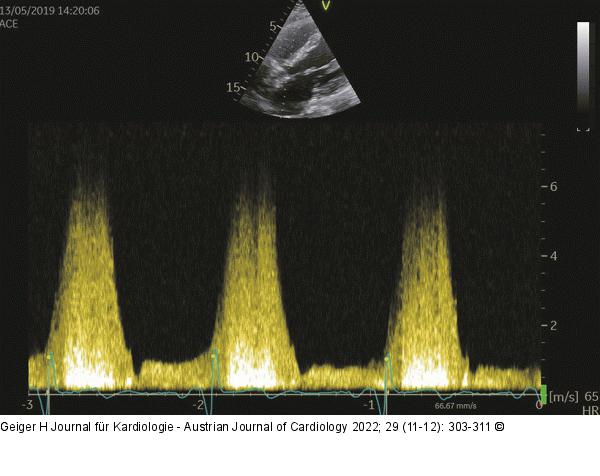

Abbildung 19: CW-Doppler - VSD Gleicher Pat. wie Abb. 18; CW-Doppler über dem VSD mit 5,5 m/s, entsprechend 120 mmHg. Nun muss man noch den systemischen RR messen (war 140 mmHg systol.), somit ist der VSD drucktrennend. |

Gleicher Pat. wie Abb. 18; CW-Doppler über dem VSD mit 5,5 m/s, entsprechend 120 mmHg. Nun muss man noch den systemischen RR messen (war 140 mmHg systol.), somit ist der VSD drucktrennend. |